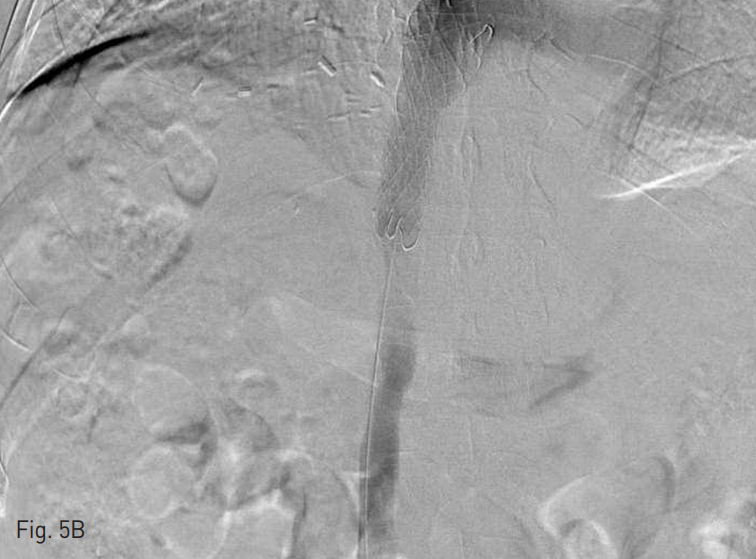

복부 전산화 단층촬영에서 간내부와 간하부의 하대정맥을 따라서 광범위한 혈전이 관찰되었고 양측 신 정맥과 장골정맥까지 혈전증이 동반되어 있었음 (Fig. 1).

Fig. 1

Diffuse thromobosis are in intrahepatic IVC (A), left renal vein (B), and both iliac veins (C)